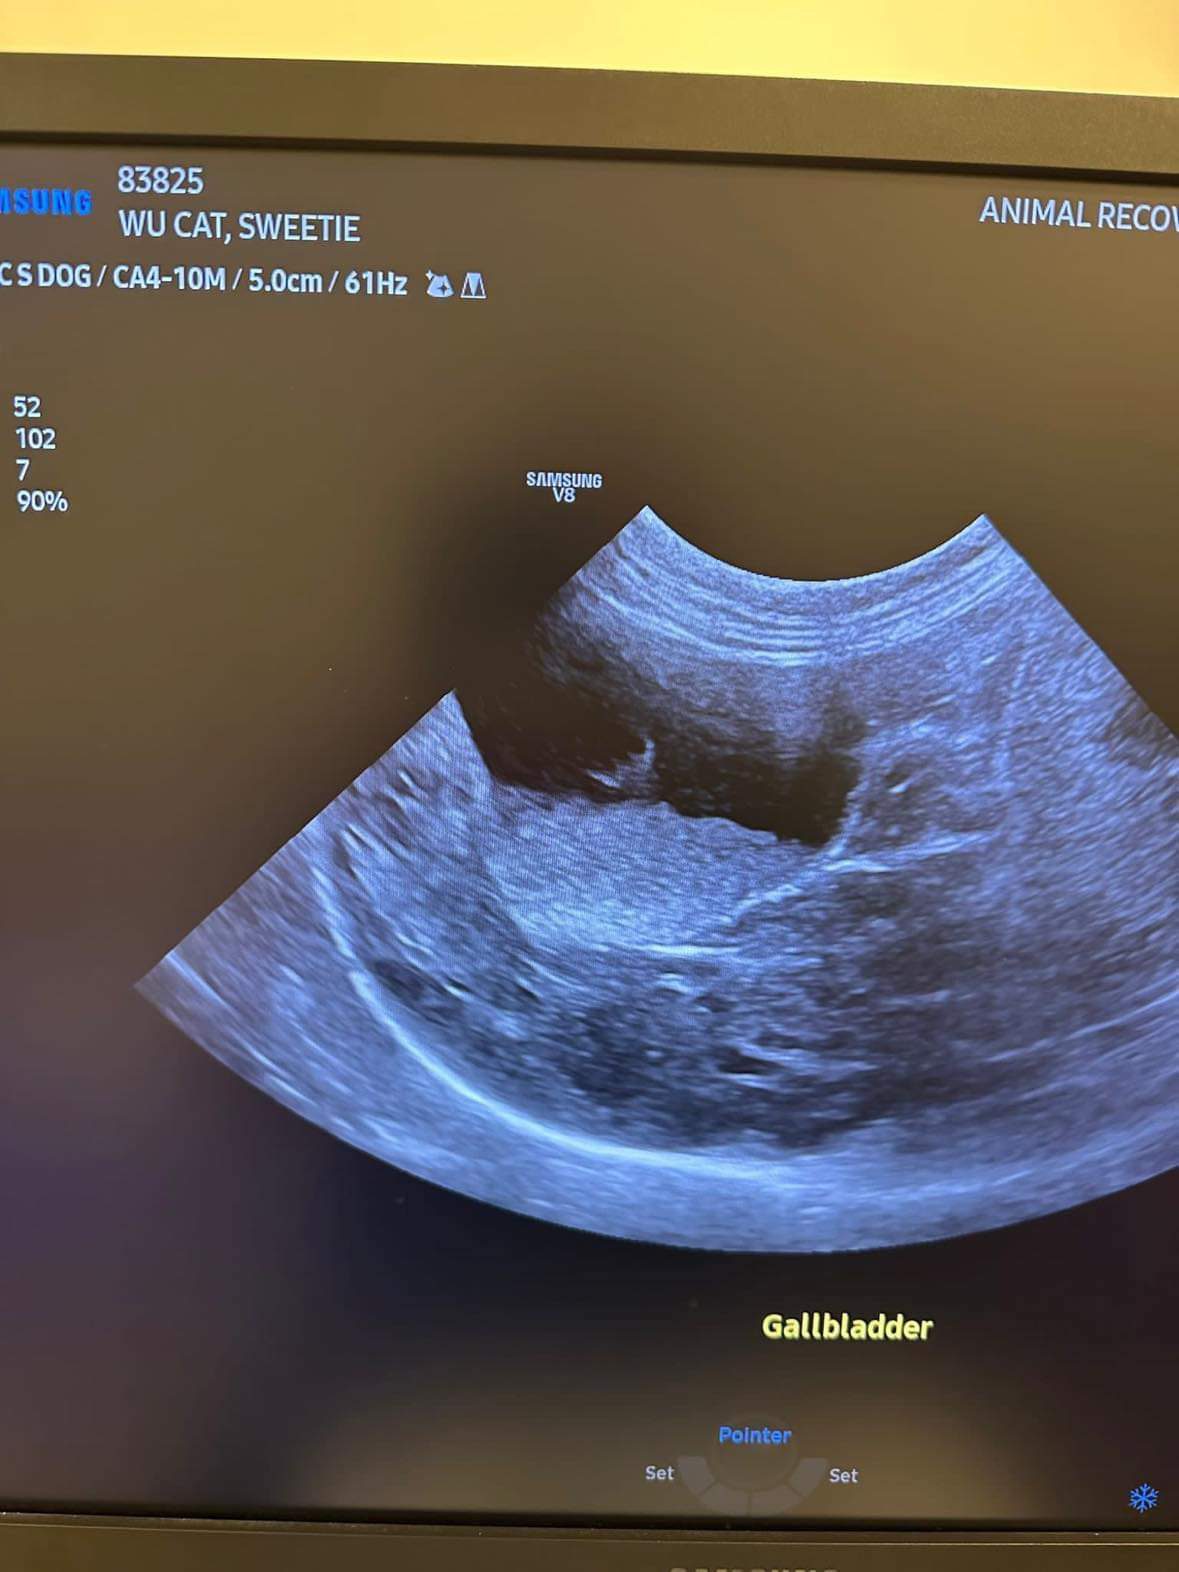

U/s done and basically not much use to me, liver got issue, kidneys got some fatty deposits which is diabetic, so insulin correct. Gall bladder got some obstruction so just start urofalk. All in must put o tube. Dr Daniel do it.

U/s still show the scary fluid ard the kidneys and there is issue w gall bladder also. As the GGT 7 but without confirming is it an obstruction cannot anyhow use. Give le obstruct will rupture.